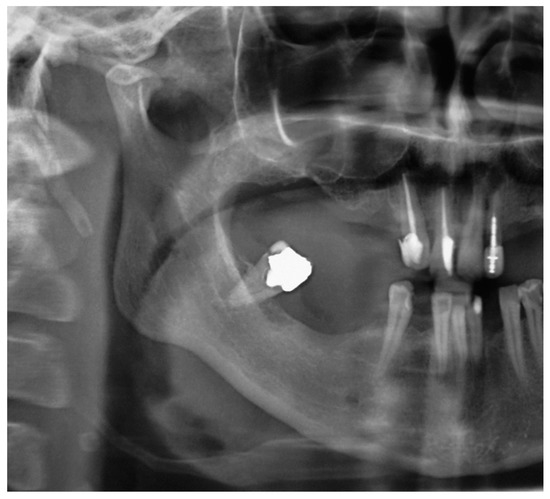

The patient’s orofacial region was thoroughly examined with no clinical findings indicating the cause of her pain episodes. However, oropharyngeal examination showed severe tenderness and pain on palpation in the right tonsillar region, with motion pain occurrence during head horizontal rotation. Panoramic X-ray acquisition showed pathological elongation of the right styloid process, like a “thorn” with a length of 49 mm by manual measurement with a ruler (Figure 1).

Patient #1 is categorized in the group confirming diagnosis of true Eagle’s syndrome and scheduled for surgery. After preparation for general anesthesia, surgery was performed by the extraoral trans cervical per via approach into the parapharyngeal space, for identification of styloid process, which was subsequently surgically removed for half of its length (~25 mm), seen in repeated panoramic X-ray acquisition (Figure 2).

Patient #2′s panoramic X-ray acquisition showed bilaterally pathological nodular elongation of the left and right styloid processes extending beyond the lower border of the mandible (Figure 3); an unerupted impacted maxillary left canine and, on the right side, the sinus mucocele was also observed. A tentative diagnosis was made that the patient had true Eagle’s syndrome due to the unusual panoramic image and pain experiences.

Figure 1. Cropped panoramic image showing pathologically elongated styloid process ending at the inner side of angle of mandible. The length of styloid process is 46 mm (conventional manual measurement with straight ruler).

Figure 3. Panoramic X-ray acquisition showing bilaterally pathological nodular elongation of the left and right styloid processes extending beyond the lower border of the mandible; an unerupted impacted maxillary left canine and, on the right side, the sinus mucocele can also be seen.